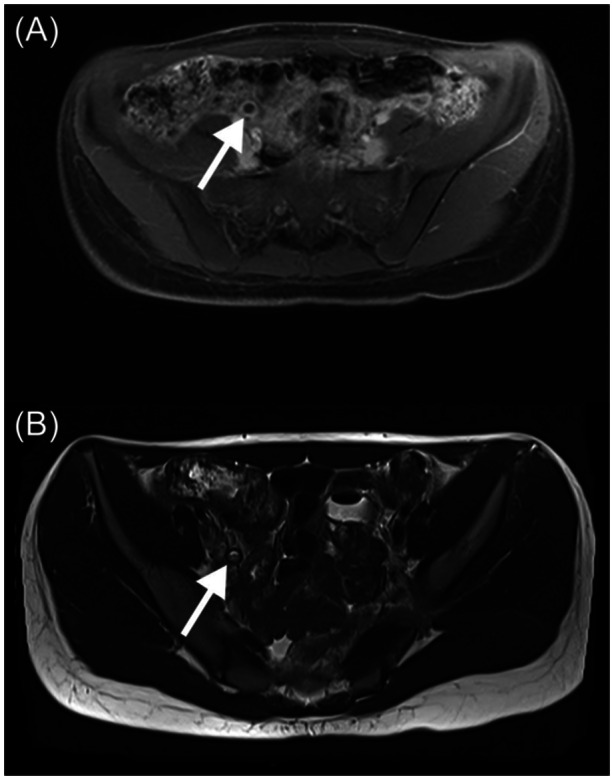

无症状阑尾炎的偶然诊断是非常罕见的,当内窥镜诊断时更是如此。这是第一个报告的病例阑尾炎偶然诊断期间结肠镜检查的儿科患者。最值得注意的是,亚临床阑尾炎的识别允许早期转介到儿科外科进行治疗,这反过来可能防止进展为急性症状性阑尾炎。

Incidental diagnosis of asymptomatic appendicitis is exceptionally rare, even more so when identified endoscopically. This is among the first reported cases of appendicitis incidentally diagnosed during colonoscopy in a pediatric patient. Most notably, the identification of subclinical appendicitis allowed for early referral to pediatric surgery for management, which in turn may have prevented progression to acute symptomatic appendicitis.